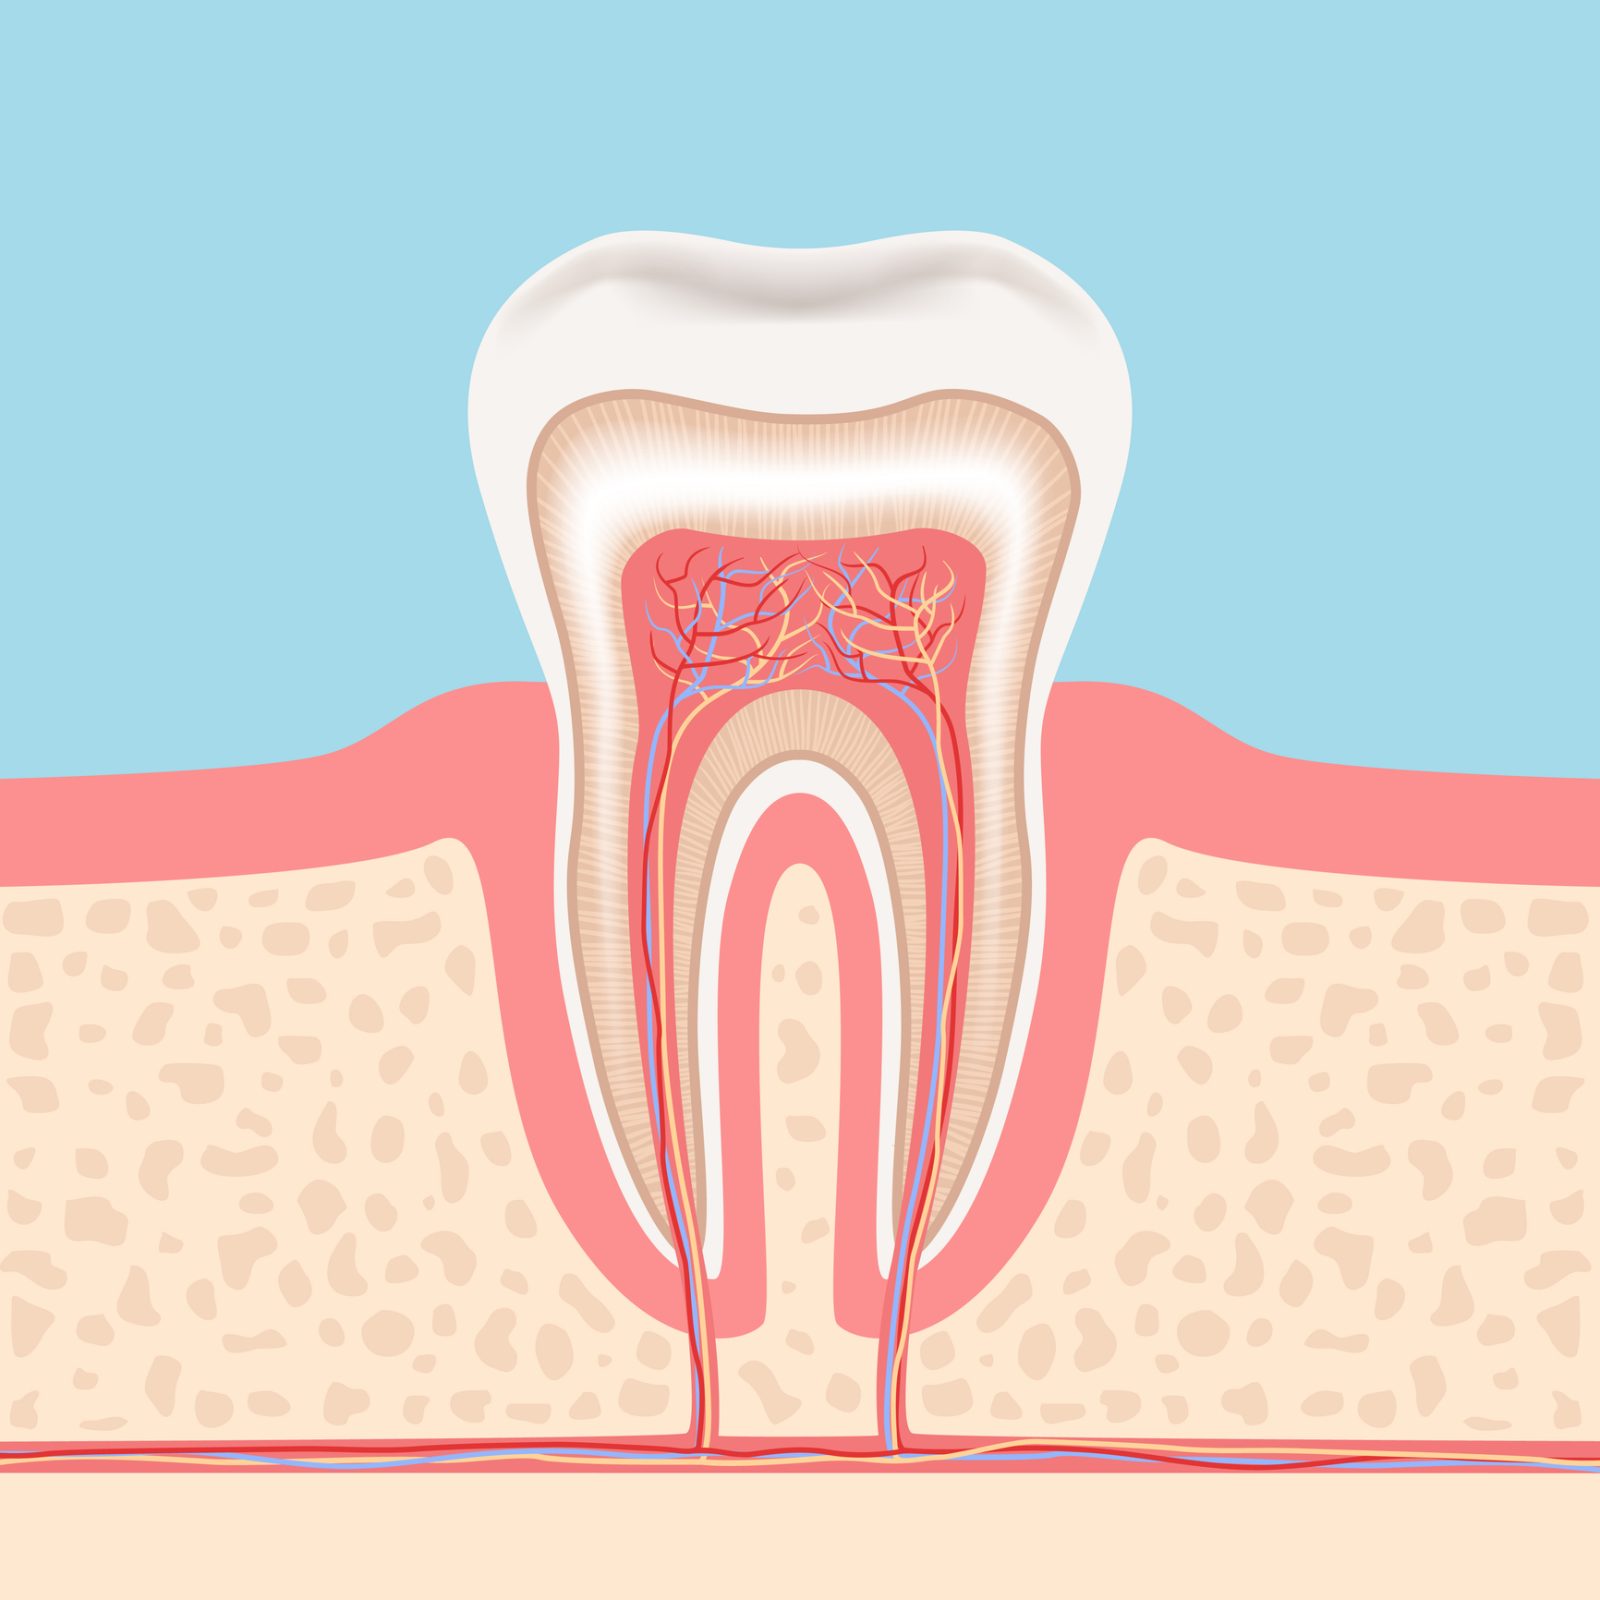

虫歯が進行して歯の内部にある神経まで到達すると、激しい痛みを感じることがあります。こうした歯から神経を取り除くのが根管治療です。この治療によって痛みは一時的に和らぎますが、治療を受けた患者さんの中には、「神経を取ったはずなのに再び痛くなってきた」といったケースも少なくありません。

歯の神経は、歯に栄養を供給するという非常に重要な役割を担っています。神経を失うことは、栄養を失うことも意味します。その結果、栄養を受け取れなくなった歯は徐々に弱くなっていきます。もし炎症が再発した場合、弱くなった歯を再度削ることになり、歯はどんどん弱くなります。時間の問題で、きっと割れてしまうでしょう。

実際に根管の画像をご覧ください。歯の中に存在する黒い筋が、これが根管です。

根管は非常に複雑な形状をしており、特に狭い部分では直径が1mmにも満たないことがあります。このような繊細な根管から、感染した組織を完全に除去するのは容易ではありません。しかし、多くの歯科医院ではこの作業を肉眼で行っているため、どうしても限界があります。その結果、日本の根管治療の成功率が低い原因の一つとも言われています。